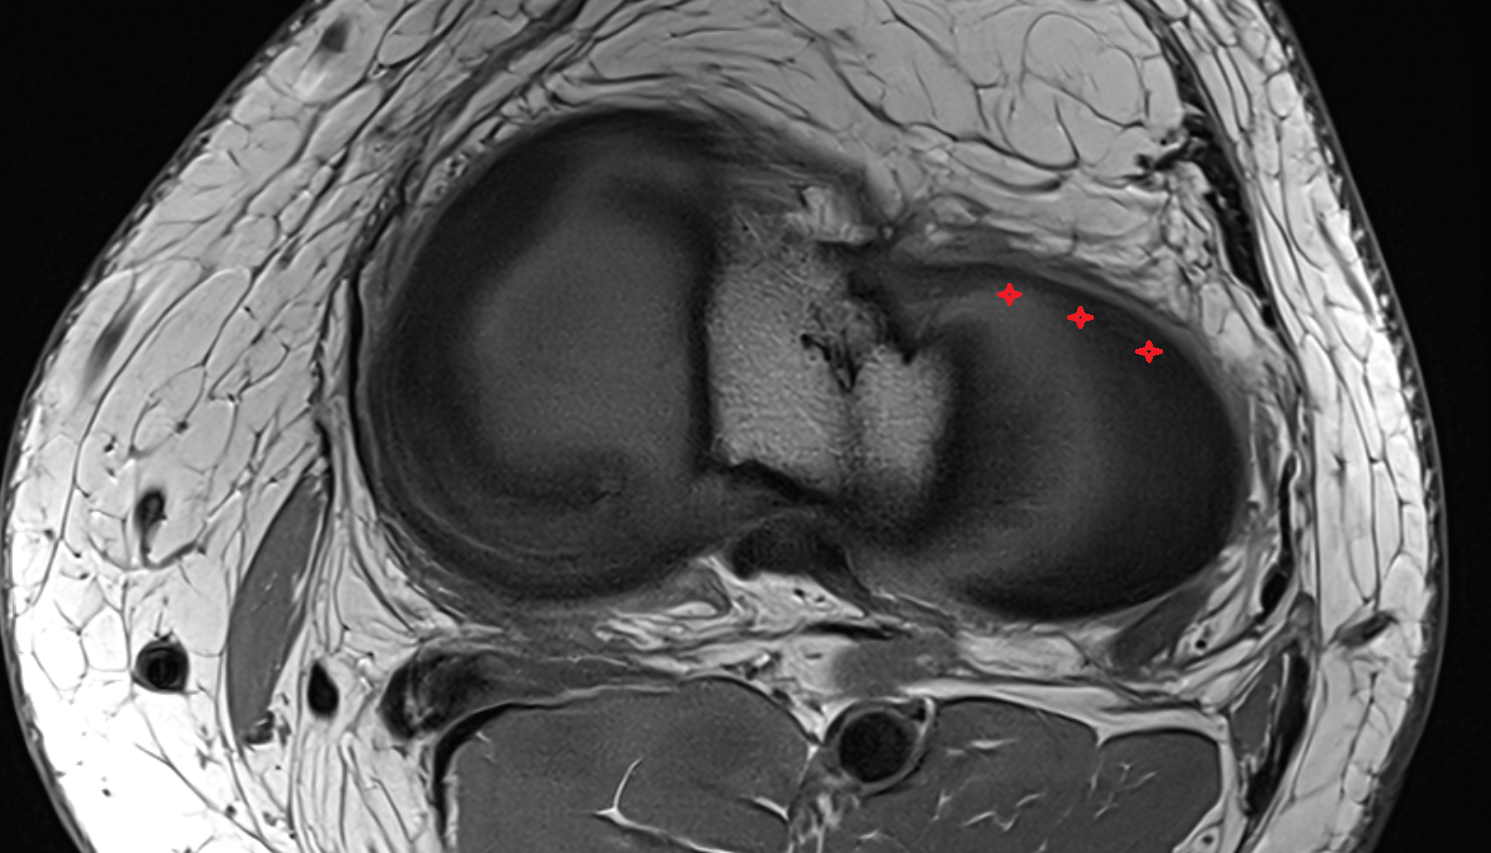

- Meniscus cartilage

- Medial meniscus

- Lateral meniscus

- Anterior horn of lateral meniscus

- Posterior horn of lateral meniscus

- Body of lateral meniscus

- Anterior root of lateral meniscus

- Posterior root of lateral meniscus